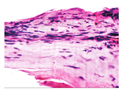

患者男,57岁。2014年1月于河南省立眼科医院就诊,1个月前,自觉左眼异物感,视力下降,并发现左眼泡样隆起物,来我院就诊。追问病史,患者30年前左眼曾被扫帚击伤,未行手术治疗,全身及局部应用药物治疗,视力稍有下降。本次入院检查:视力:右眼0.8,左眼0.1;眼压:右眼16 mmHg,左眼15 mmHg。左眼鼻下方球结膜可见巨大泡样隆起,壁薄,6点至9点位角巩膜缘处可见巩膜葡萄肿,余角膜透明,前房中深,瞳孔呈梨形,向鼻下方移位明显(图1)。左眼UBM检查角膜回声清晰,中央前房深2.4 mm,瞳孔向鼻侧移位,8点位角巩膜缘处连续性中断,断口直径约0.57 mm,缺损处上方少部分向前房内弯曲,对应处见巨大结膜滤过泡,与前房沟通,呈分叶状(图4)。左眼B超见玻璃体混浊。根据患者外伤史及检查所见,诊断为:左眼前巩膜葡萄肿伴巨大滤过泡,入院行异体巩膜移植术。手术方法:因滤过泡与前房沟通,为避免切开滤过泡时眼压骤降,先行前房穿刺,降低眼压,沿角膜缘剪开鼻下方球结膜,暴露巩膜葡萄肿,发现8点处角巩膜缘穿孔,虹膜嵌顿,与周围组织粘连较重,去除虹膜表面结膜上皮,回纳部分虹膜,板层剖切穿孔周围巩膜,取相应大小异体巩膜植片间断缝合于巩膜植床。术后第3天:球结膜充血水肿,角膜透明,前房中深,瞳孔不规则,直径约4 mm(图2)。复查UBM见左眼角膜回声清晰,中央前房深2.6 mm,角巩膜未探及低回声区(图5)。术后取剖切巩膜病理检查示:巩膜穿孔,可见虹膜组织粘连,符合葡萄肿改变(图3)。

葡萄肿继续发展可造成巩膜穿孔、眼内炎等严重并发症,治疗一般采取异体巩膜修补或硬脑膜修补[5,6]。异体巩膜来源广泛,富含胶原纤维及弹性纤维,具有正常眼球弧度,不易收缩,可尽量恢复眼前节正常解剖结构,减少术后不规则散光程度,并且巩膜不含血管及特殊的纤维胶原结构,不易发生排斥反应。故本例患者选择异体巩膜修补术,术中由于葡萄肿处嵌顿虹膜严重粘连,表面被覆上皮组织,不能完全回纳入前房,故术后瞳孔不圆。外伤30年后发生前巩膜葡萄肿并自发巨大结膜滤过泡者尚未见报道,术前应详细检查,避免误诊漏诊,异体巩膜修补术可有效治疗前巩膜葡萄肿。